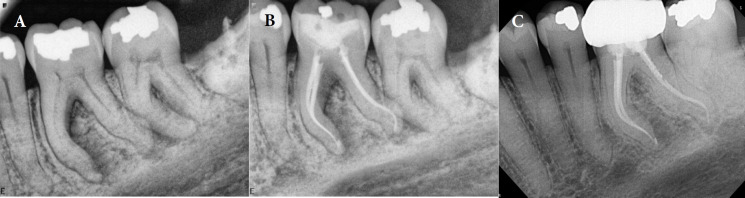

单锥体技术,也称为液压凝结技术,在牙髓病学中被广泛采用。然而,上述方法存在一定的局限性,特别是在冠状密封以及圆形横截面的水凝胶(GP)的冠状三分之一与半圆形或椭圆形横截面根管的冠状牙本质壁的适应性方面。本文通过两个病例报告介绍了冠状垂直冷凝(CVC)技术,旨在增强类似情况下 GP 与根管壁的适应性。事实上,冠状垂直冷凝技术融合了暖垂直冷凝技术和单冠技术的不同方面。在 CVC 中,放置主 GP 锥体后,立即在距根管口几毫米处插入电热载体,以去除主 GP 锥体的冠状部分。随后,使用手动堵塞器在垂直方向凝结 GP,并使用融化的 GP 回填冠状空间。CVC 技术的实施表明,GP 与管壁的冠状适应性得到了改善。上述技术似乎很有益处,尤其是在封闭严重弯曲的根管或最终预备形状为可变锥度的根管时。

The single-cone technique, also known as the hydraulic condensation technique, is widely employed in endodontics. However, the aforementioned method is presented with certain limitations; specifically concerning the coronal seal and the adaptation of the coronal third of a master gutta-percha (GP) with a round cross-section to the coronal dentinal walls of root canals with semi-round or oval cross-sections. Through two case reports, the current article introduces the coronal vertical condensation (CVC) technique; aiming to enhance GP adaptation to canal walls in similar scenarios. In fact, the coronal vertical condensation technique amalgamates the different aspects of warm vertical condensation and single-cone techniques. In CVC, following the placement of the master GP cone, an electrical heat carrier is inserted immediately a few millimeters apical from the canal orifice to remove the coronal portion of the master GP cone. Subsequently, a hand plugger is used to condense GP in the vertical dimension, and the coronal space is backfilled using melted GP. The implementation of CVC technique has demonstrated an improved coronal adaptation of GP with canal walls. The stated technique seems beneficial; especially in the obturation of severely curved canals or root canals with a final preparation shape of variable taper.